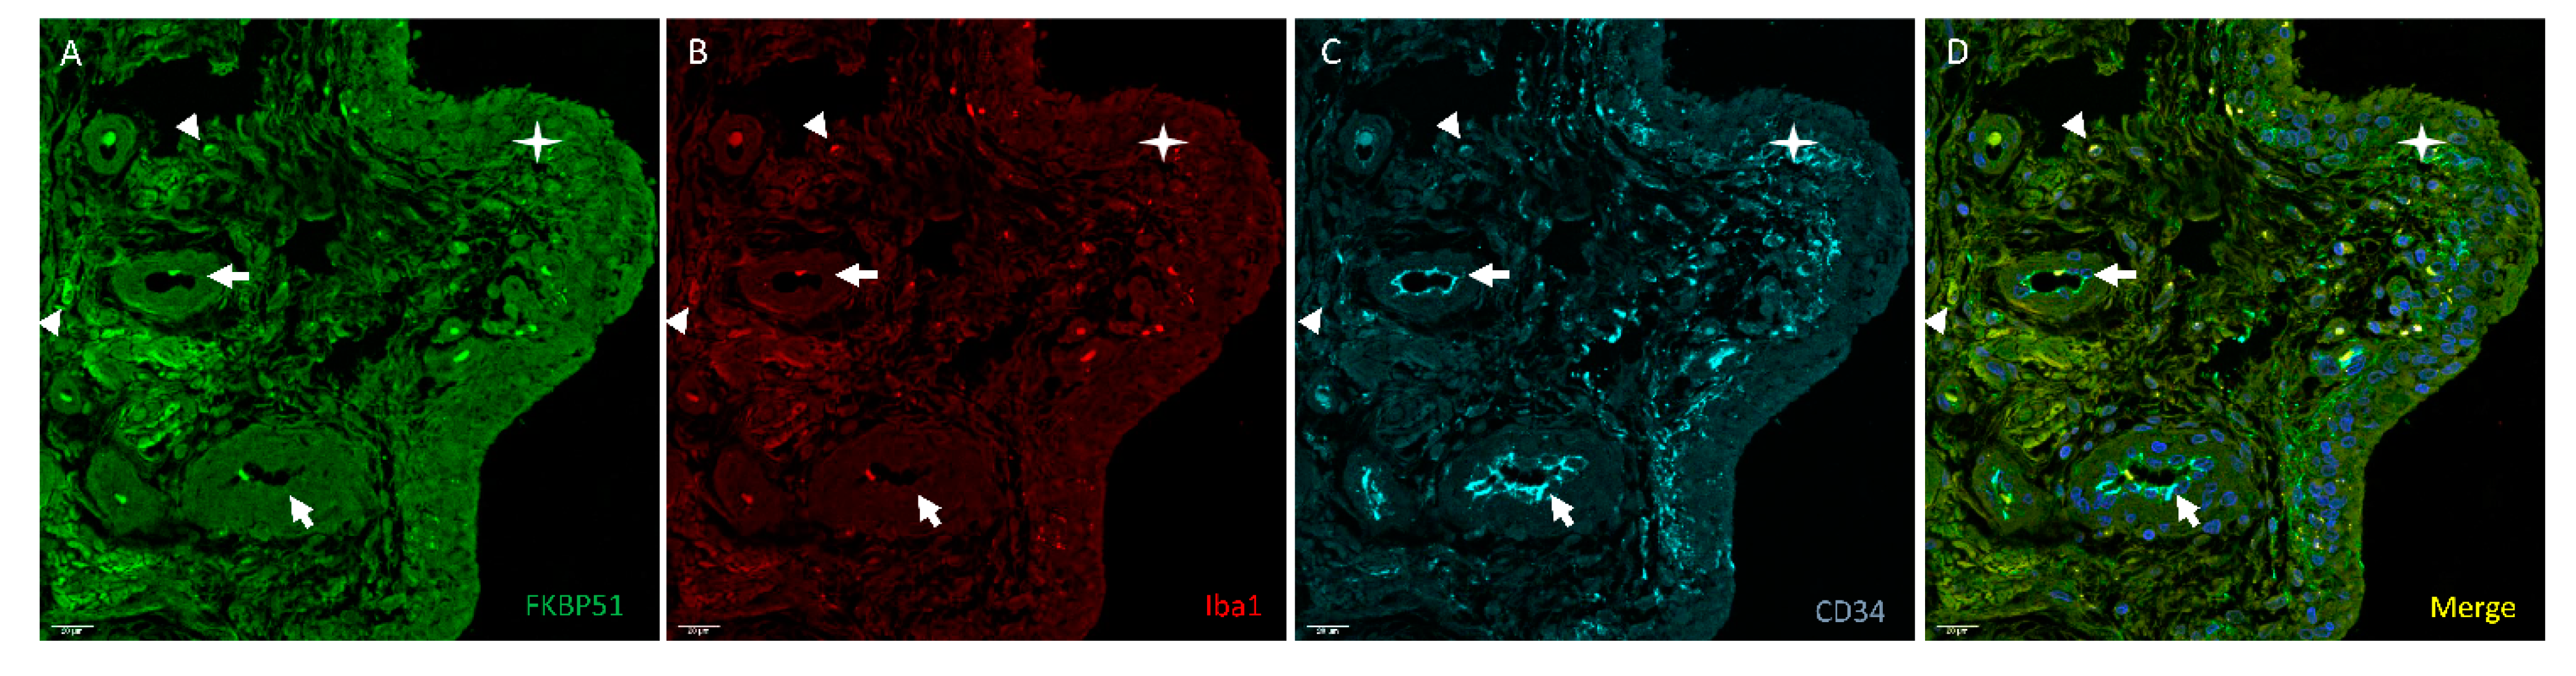

3. Results

4. Discussion